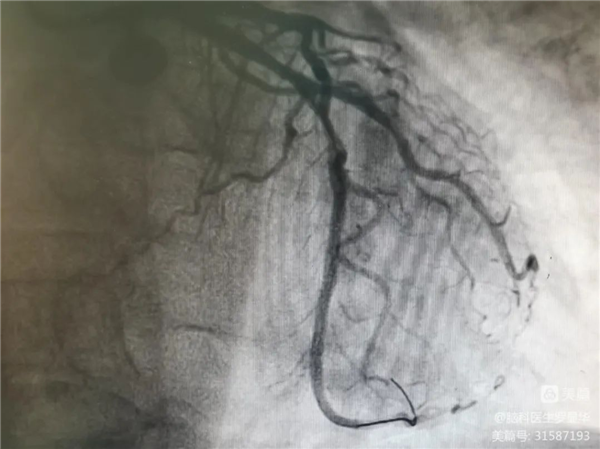

支架植入后狹窄完全解除Xbg安康新聞網(wǎng)

術(shù)后造影示狹窄解除Xbg安康新聞網(wǎng)